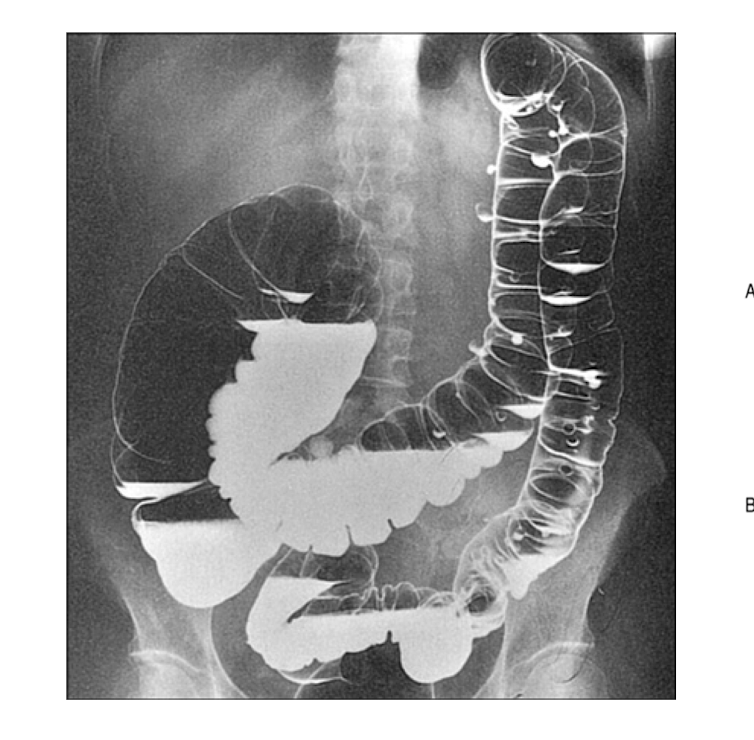

What is the normal anatomic appearance of the stomach, duodenum, jejunum, and colon?